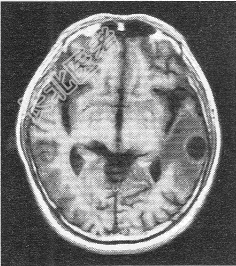

- 单项选择题患者男,72岁。肺癌术后一年余, 现出现头晕头痛,MR图像如下, 最具有可能的诊断是

B、脑转移癌